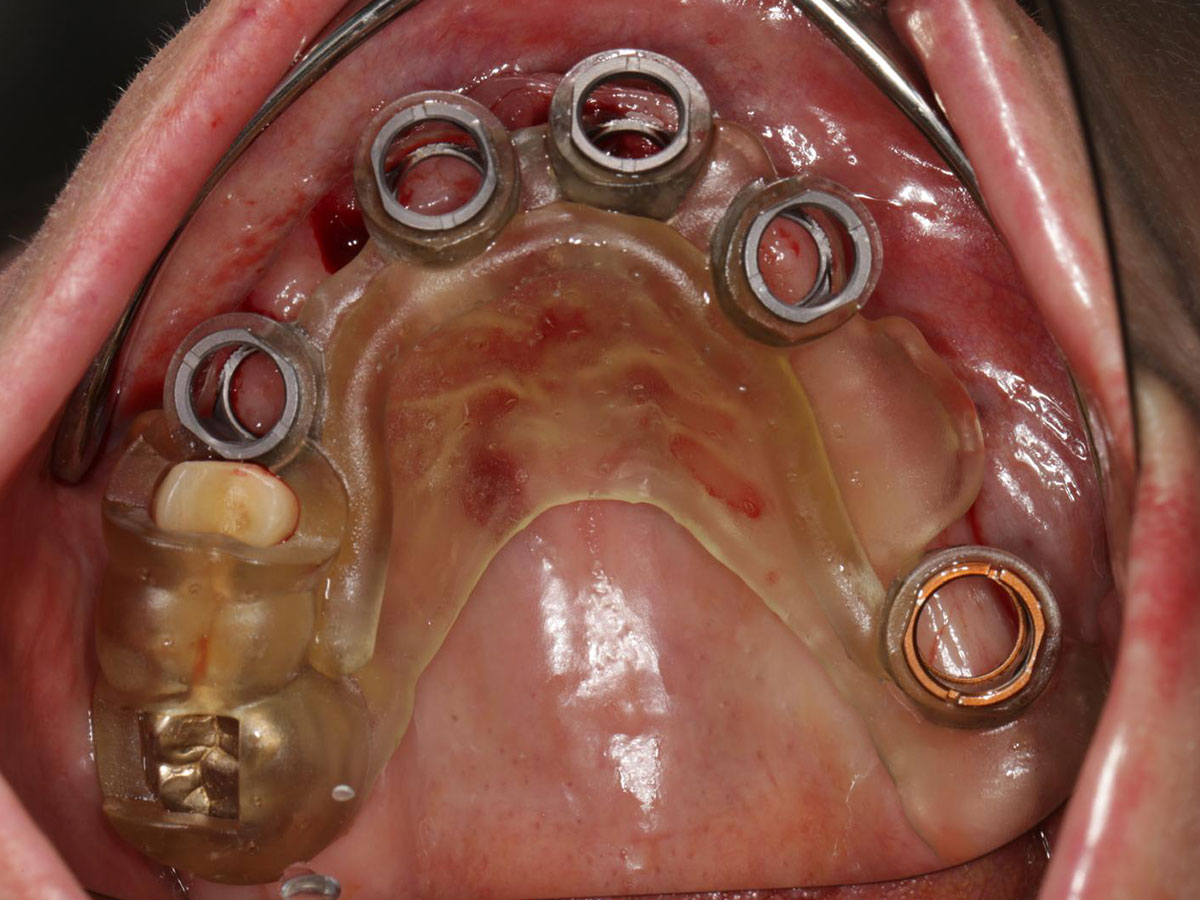

· Planungssicherheit durch digitale Simulation

· DVT- und intraorale Scandaten: Erfassung, Matching und Planung

· Virtuelle Implantatplanung unter funktionellen, anatomischen und ästhetischen Aspekten